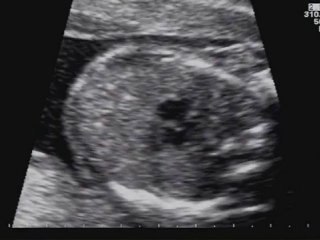

Aneurisma del forame ovale